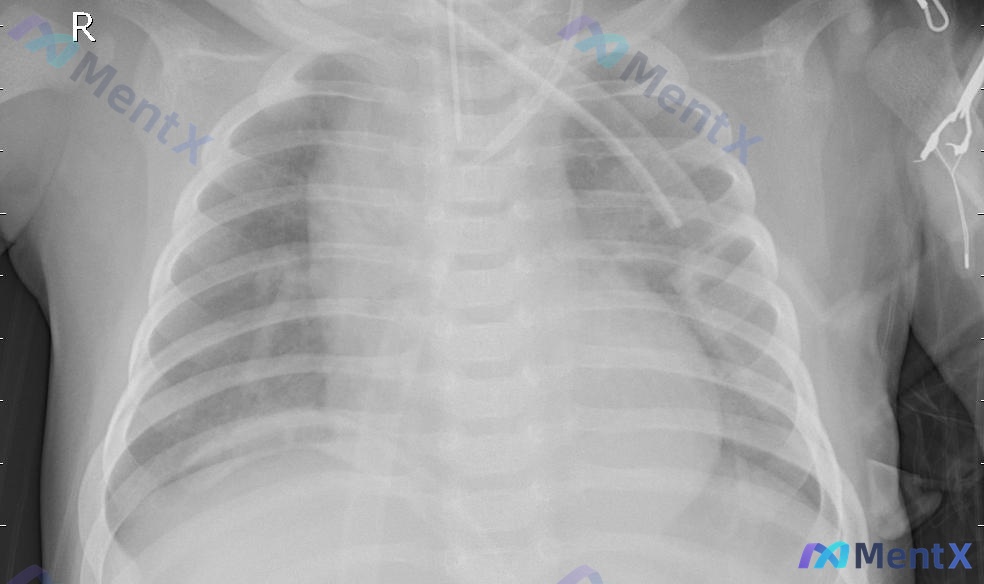

看到一份床旁胸片的资料,整理一下思路,这个病例的影像表现有点容易被带偏。 先看基本影像信息 - 投照方式:移动床旁AP位(前后位)直立摄片,有吸气相欠佳、轻微旋转,还有监测电极片和右侧胸壁的心脏植入装置(起搏器/ICD)导线伪影。 - 核心表现:双肺透亮度不均,弥漫双侧细网状间质密度增高,肺门周围及...